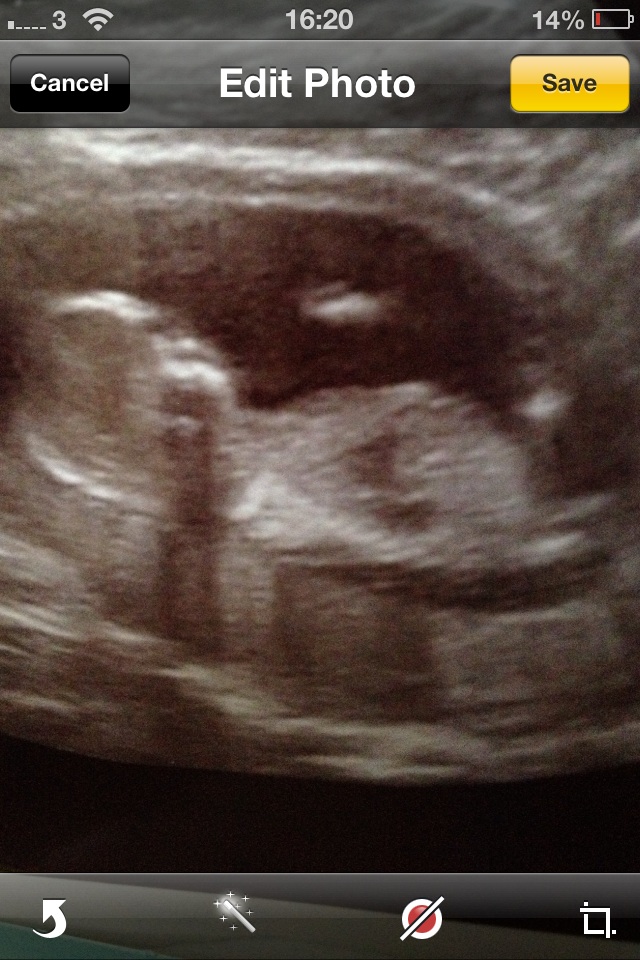

15 weeks girl or boy guesses please :)

Here is my 15 week scan pic! Hoping anyone has some ideas! :) xx